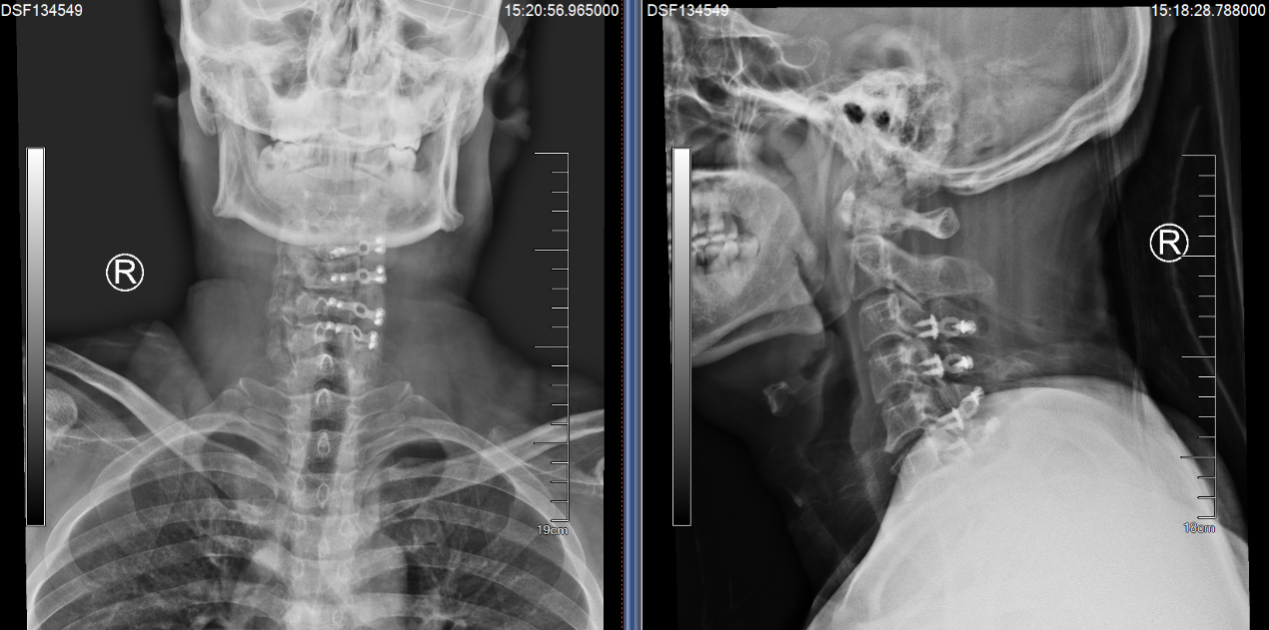

就在吕飞出院的当天,另一位症状相似的脊髓型颈椎病患者吕艳也来办理了住院手续。原来她是吕飞的亲姐姐,今年46岁。姐弟俩的症状和影像学表现都几乎相同,可见颈椎后纵韧带骨化确有一定的家族遗传倾向。吕艳告诉我们,他们姐弟这些年看过不少医生,都建议尽早手术,但因为听说颈椎手术风险极高,所以一直都选择“拖字诀”处理。这次吕飞的手术效果,给了她极大的信心和勇气,她毫不犹豫地也选择来做手术。

(姐姐的颈椎CT显示她的颈椎椎体同样存在明显的后纵韧带骨化,与弟弟不同的是,她的韧带骨化程度更严重)

(吕姐的接受的手术与吕弟一样,C3~6椎管扩大成形术。)